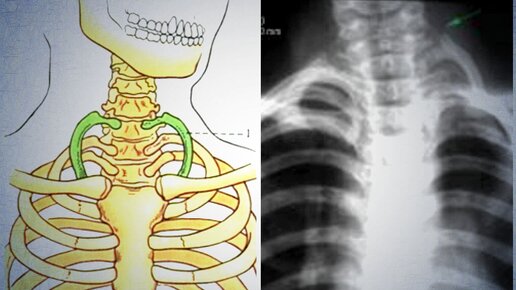

Грудная клетка взрослого человека состоит из 12 пар рёбер, разделяемых на 3 отдела – истинные (крепятся к грудине), ложные и колеблющиеся (имеющие свободные концы). По данным статистики каждый 200-й человек рождается с дополнительным ребром...

Лишние или запасные? Почему дополнительные ребра у человека считается патологией развития. Анатомия — наука точная и не оставляет сомнений: у человека 12 пар ребер, то есть всего 24 ребра. Но бывают исключения. Например, синдром «ребра Адама» — анатомическая аномалия, когда в скелете насчитывается лишнее ребро. Случается и обратная ситуация — у людей могут отсутствовать 11-я или 12-я пара ребер. В скелете человека более 200 костей. Ребра — это длинные изогнутые плоские кости, состоящие из костной части и реберного хряща...